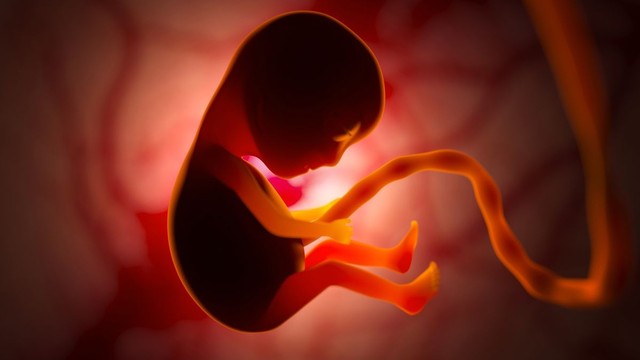

Thai bị thiếu máu là một trong những tình trạng y khoa đáng lo ngại trong thai kỳ, có thể dẫn đến nhiều biến chứng nghiêm trọng như suy tim thai, phù thai, thậm chí là đe dọa tính mạng của thai nhi nếu không được phát hiện và can thiệp kịp thời.

Thai nhi cử động nhiều có sao không? Là băn khoăn của nhiều mẹ bầu khi cảm nhận bé đạp liên tục trong bụng. Đây có thể là dấu hiệu cho thấy thai đang phát triển tốt, nhưng đôi khi cũng khiến mẹ lo lắng về những bất thường tiềm ẩn cần được theo dõi.

Mang thai tuần 15 là thời điểm nhiều mẹ bầu bắt đầu cảm thấy yên tâm hơn vì đã đi qua giai đoạn ốm nghén của 3 tháng đầu. Tuy nhiên, không ít người vẫn băn khoăn thai 15 tuần đã an toàn chưa, thai nhi phát triển thế nào, cơ thể mẹ thay đổi ra sao và cần lưu ý gì để bảo vệ sức khỏe trong giai đoạn này.

Thai 16 tuần nặng bao nhiêu là thắc mắc của nhiều mẹ bầu khi bước vào giai đoạn giữa tam cá nguyệt thứ hai. Lúc này, em bé đang phát triển nhanh về chiều dài, cân nặng và các cơ quan quan trọng. Việc theo dõi chỉ số thai giúp mẹ hiểu rõ sự tăng trưởng của con theo từng tuần.

Dấu hiệu thai phát triển tốt 3 tháng đầu là mối quan tâm hàng đầu của nhiều mẹ bầu, đặc biệt là những người mang thai lần đầu. Bài viết dưới đây sẽ giúp mẹ nhận biết các dấu hiệu tích cực cũng như những lưu ý quan trọng trong tam cá nguyệt đầu tiên.

Trong y học, có những hiện tượng hiếm gặp đến mức chỉ được ghi nhận qua rất ít ca bệnh trên thế giới, và thai nhi hóa đá là một trong số đó. Đây là tình trạng đặc biệt xảy ra khi thai ngoài tử cung bị chết nhưng không được đào thải, tồn tại trong cơ thể người mẹ suốt nhiều năm. Vậy thai nhi hóa đá là gì và vì sao hiện tượng này lại được xem là một trường hợp hiếm trong y khoa?

Thận ứ nước ở thai nhi là một trong những bất thường hệ tiết niệu thường được phát hiện qua siêu âm thai kỳ. Việc hiểu rõ tại sao thai nhi bị thận ứ nước, cách chẩn đoán và chăm sóc phù hợp sẽ giúp gia đình chủ động phối hợp với bác sĩ, đảm bảo an toàn cho trẻ ngay từ giai đoạn đầu đời.

Thai nhi mọc chồi ở mặt là dấu hiệu bất thường về não ở thai nhi với tỷ lệ hiếm gặp được ước tính chỉ xảy ra ở 1/250 phôi, tình trạng này thường dẫn đến việc thai nhi ngừng phát triển hoặc sảy thai sớm.